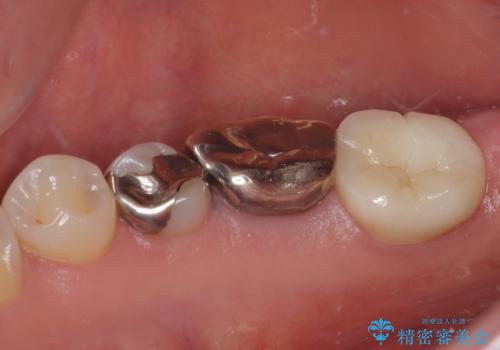

- 右下の銀歯が取れたとのことで来院された患者様です。脱離をしたメタルインレーを戻してみましたが不適合を認めました。メタルインレーの範囲が大きく、残っている歯の範囲を考慮してオールセラミッククラウンにて補綴治療を行っていくことにしました。

拡大鏡視野下で虫歯の除去を行い、オールセラミッククラウンに適した形に整えました。

歯と歯茎の間に圧排糸と言われる糸を入れてシリコーン印象材にて型どりをしました。